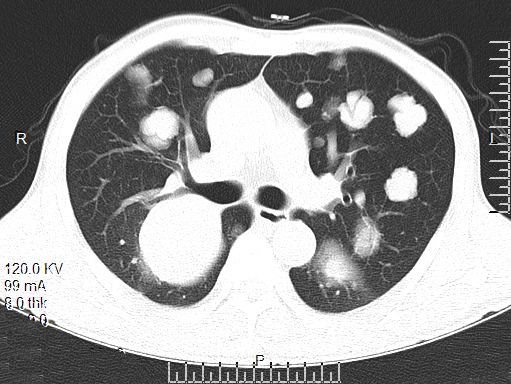

[影像描述]

双肺多发转移灶,大小不等,呈棉花团样

CT表现为粟粒、单发、多发大小不等结节,呈圆形或椭圆形,密度均匀、轮廓清楚,肺野为著。

1、肺内单发或多发球型结节影,大小不一,边缘光滑,密度均匀,多分布于肺外围

2、肺内软组织团块影!单发或多发,有分叶或毛刺,部分有空洞